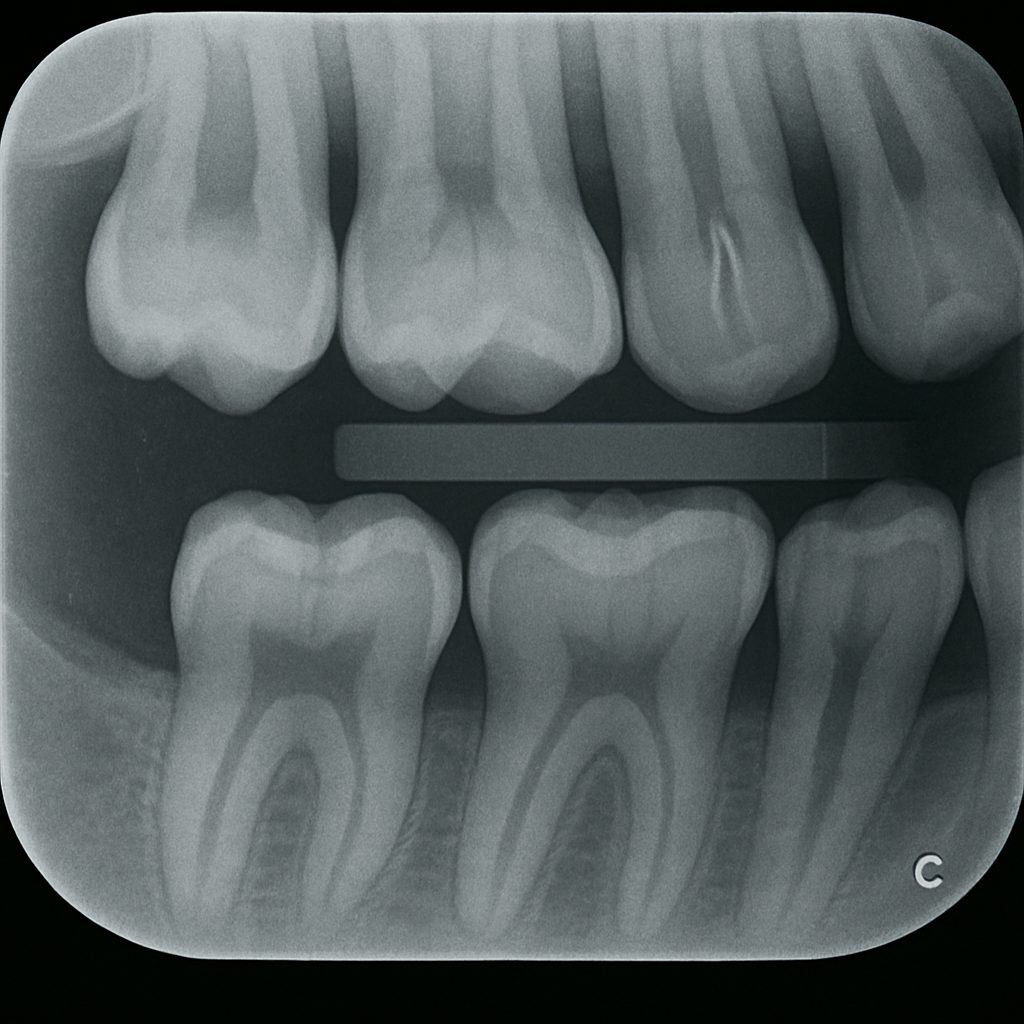

特に「咬翼法(こうよくほう)」と呼ばれるレントゲン撮影法は、隣接面の虫歯を発見するのに非常に有効です。

咬翼法(バイトウイング法)によるレントゲン画像。上下の臼歯の歯冠部と隣接面が明瞭に写っており、虫歯の早期発見に有効です。